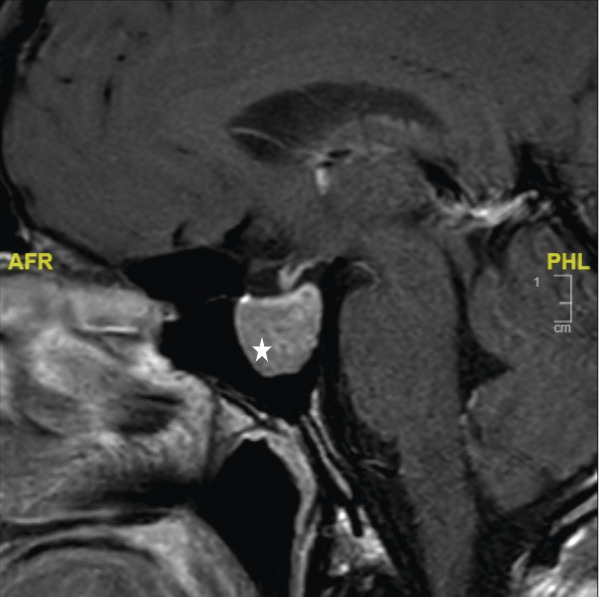

• Il mesure 1,91 m et pèse 92 kg. L’examen révèle une cyphose et une scoliose (fig. 1). Un prognathisme, une macroglossie, une hypertrophie des golfes frontaux, un élargissement des mains (fig. 2) et des pieds (il chausse du 47) ainsi que des sueurs nocturnes sont également constatés.